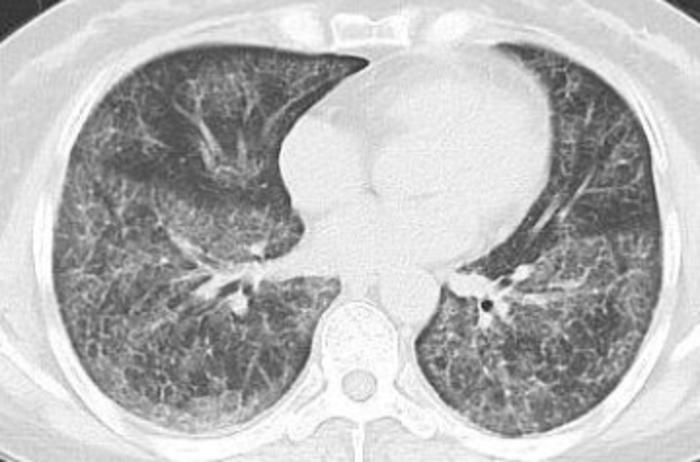

病例六、肺泡蛋白沉积症。

双肺弥漫性磨玻璃影,呈现地图样分布,可铺路石样改变。